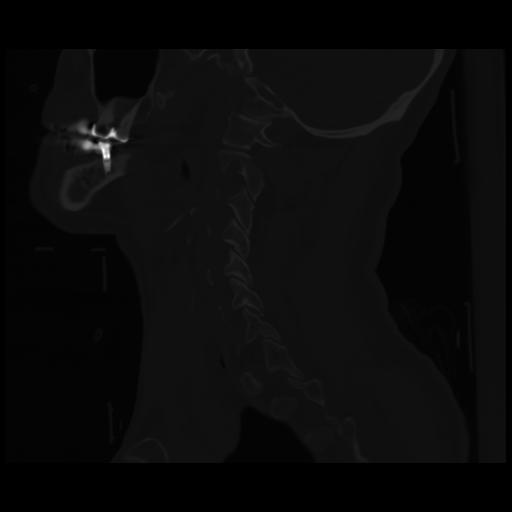

14 P.BLANDAS,,Sagittal,2.000,P.BLANDAS,Sagittal,